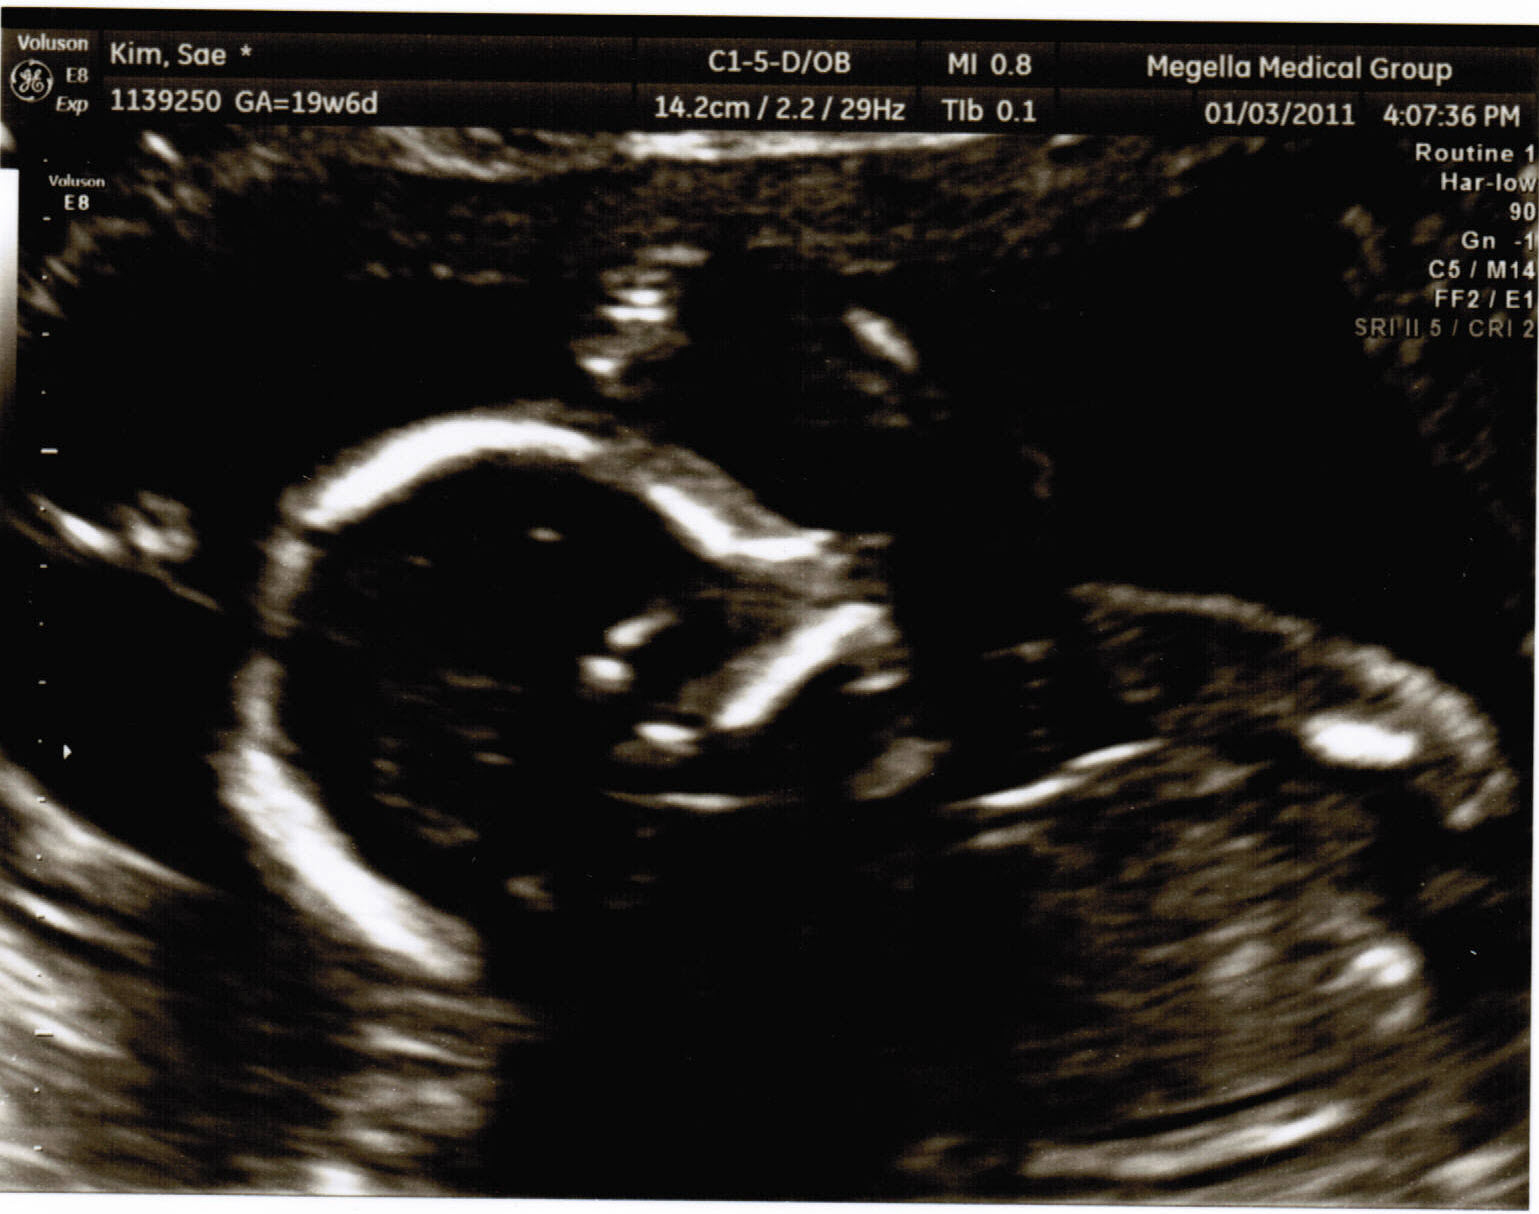

So this is it. The day we find out if it’s a boooooy or girrrrrrl!! Very interesting day, and I’ll tell you why. So we’re going through the whole sonogram process again checking the baby’s size, heart and movements. Yeah, yeah, yeah okay so i just wanted to say “come on lady just get to the point!” But anyway, as she moved into the lower Netherlands of the baby, i begin to stare hard, staring, trying to focus, then finally, i friggen see nothing. So i just look at the doctor, “weeeell?” All this while Lisa just lays there saying nothing. No expression. Any guy would be happy with a boy, as were the case with me, but i somewhat was convinced due to that fact of Lisa’s boasting of how a girl would be that much better and sweeter, swayed my intentions of somewhat wanting a girl a little more. Anyway, i’m still staring at the doctor, then at the screen, then back at the doctor, then she speaks “Okay so what you’re having is a ……… …… .. GIRL! Hearing the news I became sooooo happy, giddy, and couldn’t keep still. “A girl? Really? A girl? Yeeeeeees!” Okay, so all this time i was assuming that Lisa and I were on the same page and slightly leaning toward wanting to have a girl. But as I am celebrating I look over to her to expect a somewhat similar reaction, but, she just has no enthusiasm at all and is like ” a girl? really? a girl?